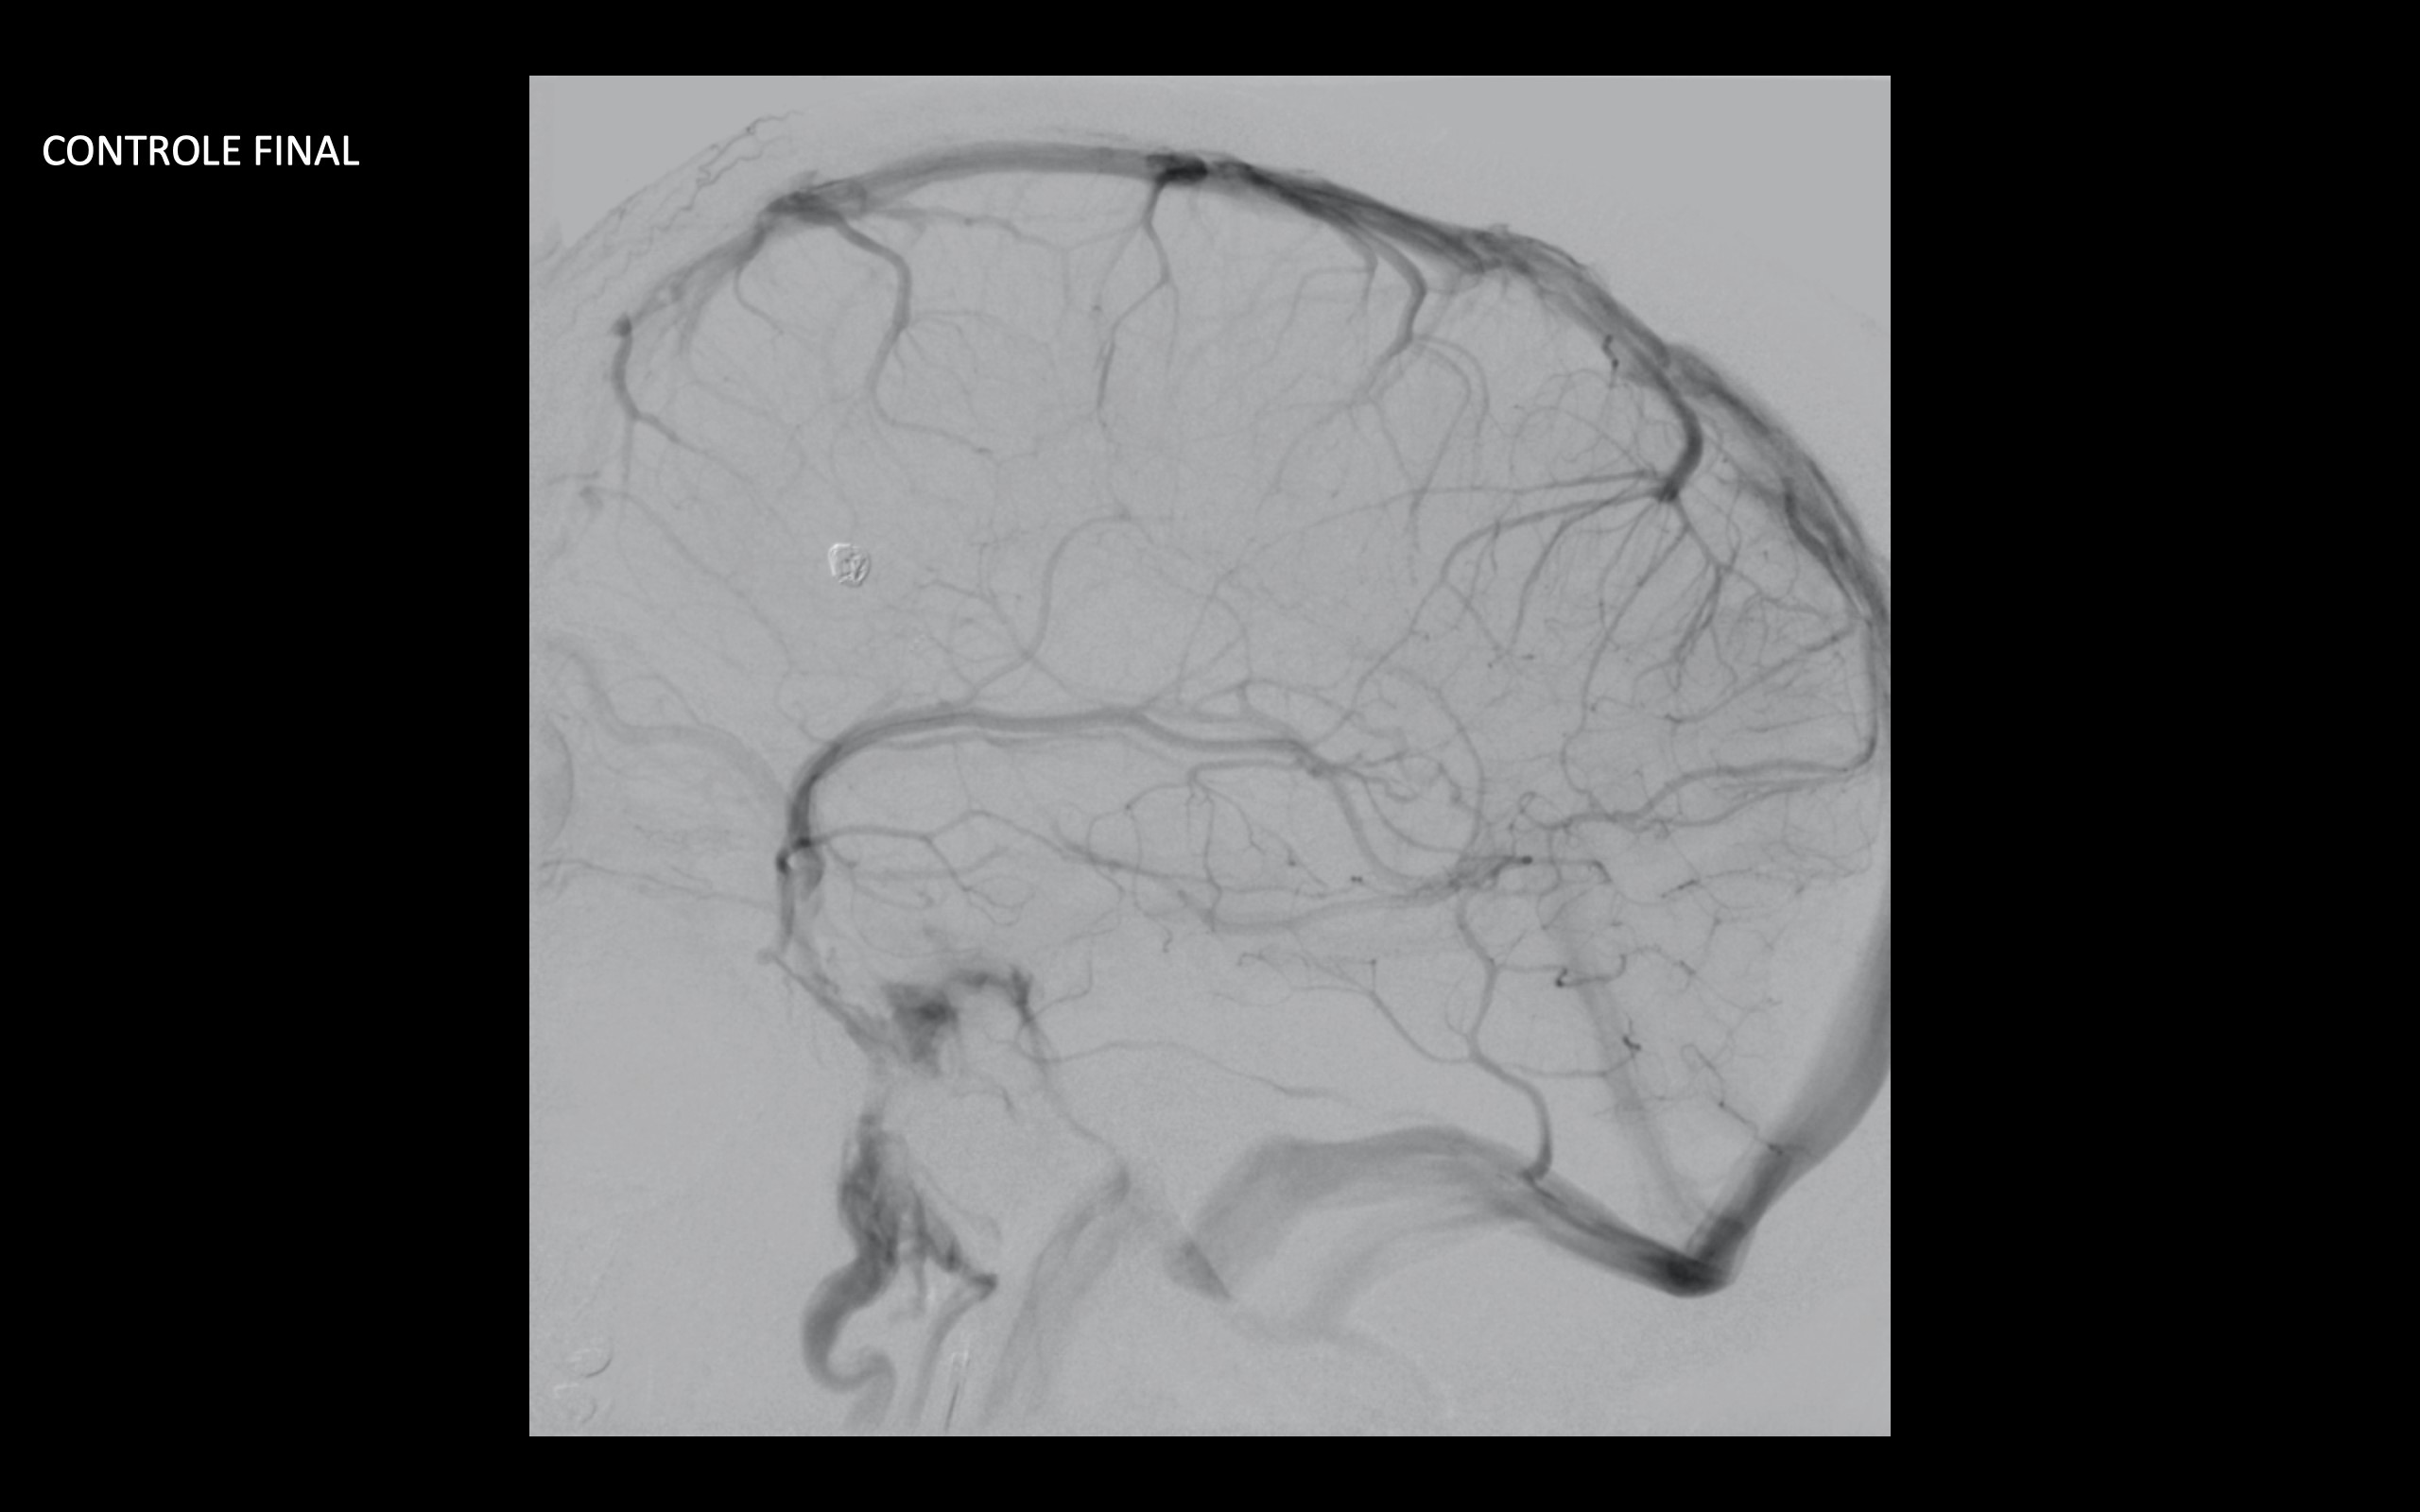

Realizado angiografia cerebral e reconstrução 3D sendo evidenciado um aneurisma de colo largo com ramo frontal emergindo do colo do aneurisma. Baseado nessas característica, foi optado por tratamento com stent redirecionado de fluxo Fred Jr., associado a micromolas de platina devido o importante inflow do ramo frontal.

Feito duplo acesso femoral e cateterismo da carótida esquerda, seguido de microcateterismo distal ao aneurisma com Headway 21 para o implante do stent, bem como do saco aneurismático para a deposição das micromolas.

Implantado um stent 2,5 x 18mm conforme programação 3D. O procedimento transcorreu sem intercorrência, mantendo a patência dos vasos envolvidos.